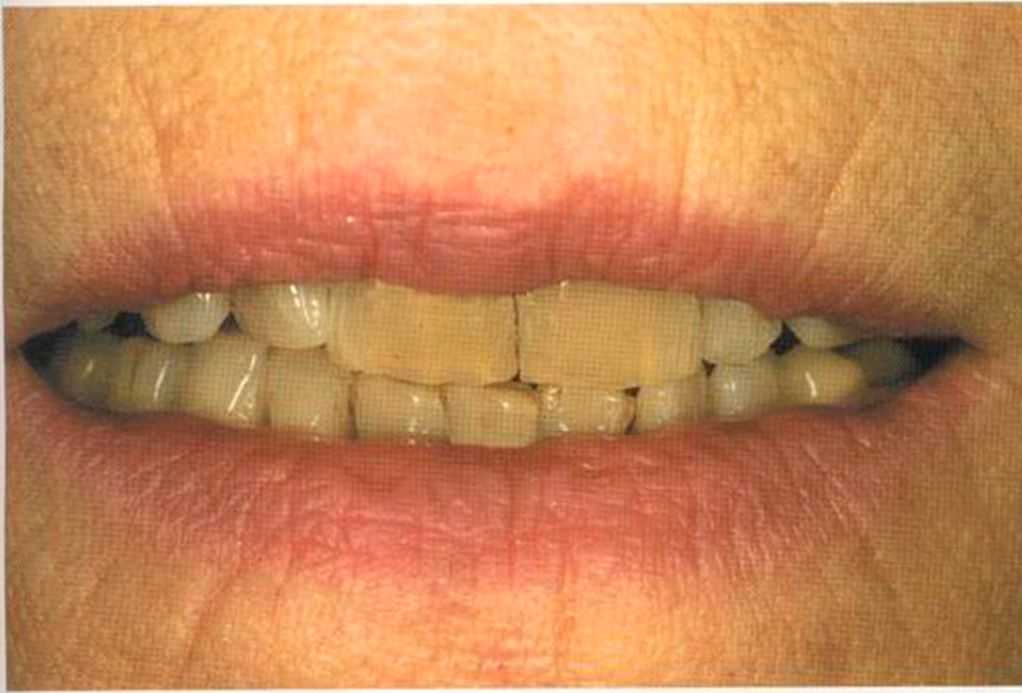

Окончательный результат и естественный цвет губ. Женщина была очень счастлива и довольна своим новым внешним видом. Наконец мечта осуществилась — нет больше этих щелей на видимом участке. Всей нашей команде было очень приятно видеть радость в ее глазах.

Эта женщина пришла в клинику доктора Лангханке с металлокерамической реставрацией.

Ей не нравились типичные в таких случаях темные края коронок и опаковость керамики.